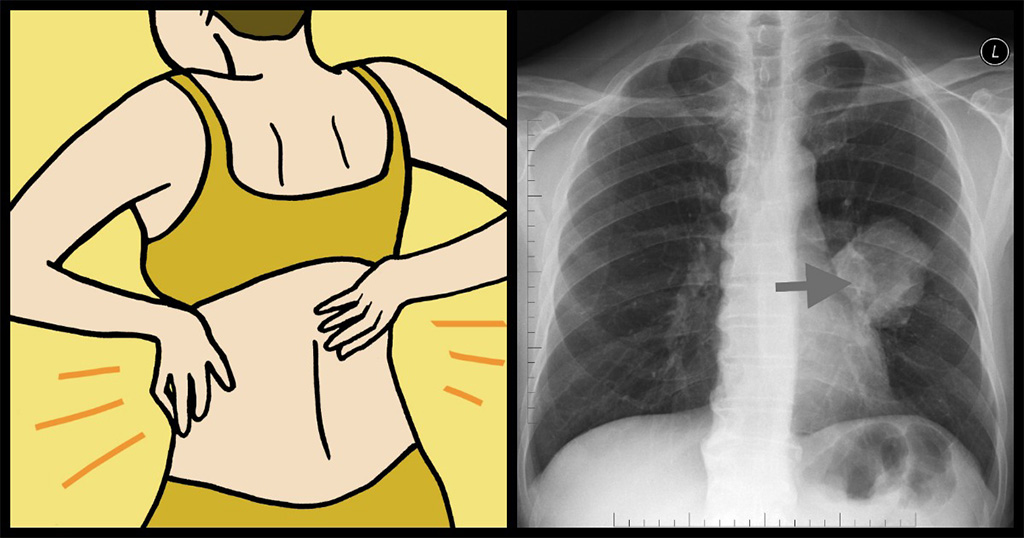

9 ύπουλα σημάδια του καρκίνου των πνευμόνων που κάθε γυναίκα οφείλει να γνωρίζει

Το πιο σημαντικό, είναι να καταλάβουμε ότι το γυναικείο σώμα μπορεί να εμφανίσει διαφορετικά συμπτώματα από το ανδρικό. Ο καρκίνος των πνευμόνων, για παράδειγμα, σκοτώνει περισσότερες γυναίκες σε έναν χρόνο, από κάθε άλλη μορφή καρκίνου. Λίγες γυναίκες, όμως, γνωρίζουν τα συμπτώματα και ειδικά εκείνα που εμφανίζονται στο γυναικείο σώμα.

#4 Πόνος στην πλάτη και τους ώμους

Λογικά δε θα σχετίζατε ποτέ τον πόνο της πλάτης με τους πνεύμονές σας, αλλά για τις γυναίκες, ο αιχμηρός πόνος στην περιοχή των ώμων, μπορεί να υποδηλώνει πως κάτι δεν πηγαίνει καλά. Αυτό συμβαίνει γιατί οι γυναίκες είναι επιρρεπείς σε μια μορφή πνευμονικού καρκίνου, που ονομάζεται αδενοκαρκίνωμα.

Οι όγκοι αυτού του καρκίνου αναπτύσσονται στα εξωτερικά στρώματα των πνευμόνων, οπότε μπορεί να ασκήσουν πίεση στα πλευρά και τη σπονδυλική στήλη.

#8 Πόνος στο στήθος

Όπως αναφέραμε και παραπάνω, τα συμπτώματα των αδενοκαρκινώματων μερικές φορές διαφέρουν λίγο από άλλα είδη πνευμονικού καρκίνου. Μπορεί να προκαλέσουν πόνο στο στήθος, όπως τον πόνο στην πλάτη, και μπορεί επίσης να οδηγήσει σε υπεζωκοτική συλλογή, μία επώδυνη κατάσταση, όπου προκαλείται φλεγμονή στην επένδυση των πνευμόνων.Αν αντιμετωπίζετε επίμονο πόνο σε ένα συγκεκριμένο σημείο των πλευρών σας, μάλλον ήρθε η ώρα να αναζητήσετε και μια δεύτερη γνώμη.